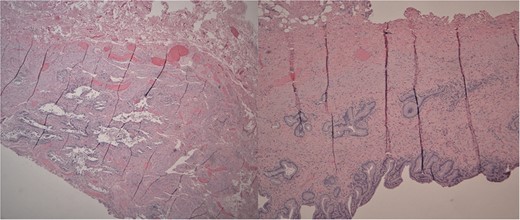

Left: Low power H&E of cystically dilated benign biliary glands accompanied by smooth muscle hypertrophy of the gallbladder wall consistent with adenomyomatous hyperplasia. Right: Low power section of fibrotic gallbladder wall with chronic inflammation consistent with chronic cholecystitis.

Macroscopically, the gallbladder was congested with purple discoloration, filled with multiple black bosselated calculi and a 0.7-cm fundic polyp. Microscopy revealed AMH, a reactive nonneoplastic lesion characterized by cystically dilated biliary glands accompanied by smooth muscle hypertrophy of the gallbladder wall. AMH is found in approximately 10% of cholecystectomies [9]. Symptoms of AMH are generally nonspecific. Most patients present with right upper quadrant abdominal pain. Our patient had the fundal variant of AMH, which is most common.